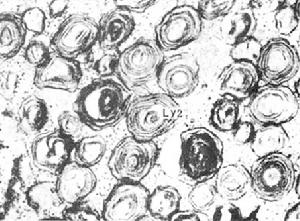

4.組織病理學檢查 急性播散性患者的肺、肝、脾、骨髓和淋巴結中有大量組織細胞浸潤。細胞內外有大量的孢子非急性病例有上皮樣細胞肉芽腫形成。中性粒細胞、淋巴細胞、漿細胞、巨噬細胞和Langerhans巨細胞內也可含有孢子,但數目較少,大小也不一。陳舊損害中大多有組織腦漿菌瘤內有少量病原菌,周圍有纖維化。HE染色見細胞內孢子呈球形,略嗜鹼性,外圍的暈環為染色時退縮所致而並非真正的莢膜PSA和GMS染色清楚,呈現圓形或卵圓形酵母樣孢子,2~5μm直徑。可能有單芽,芽頸細,周圍無暈環。